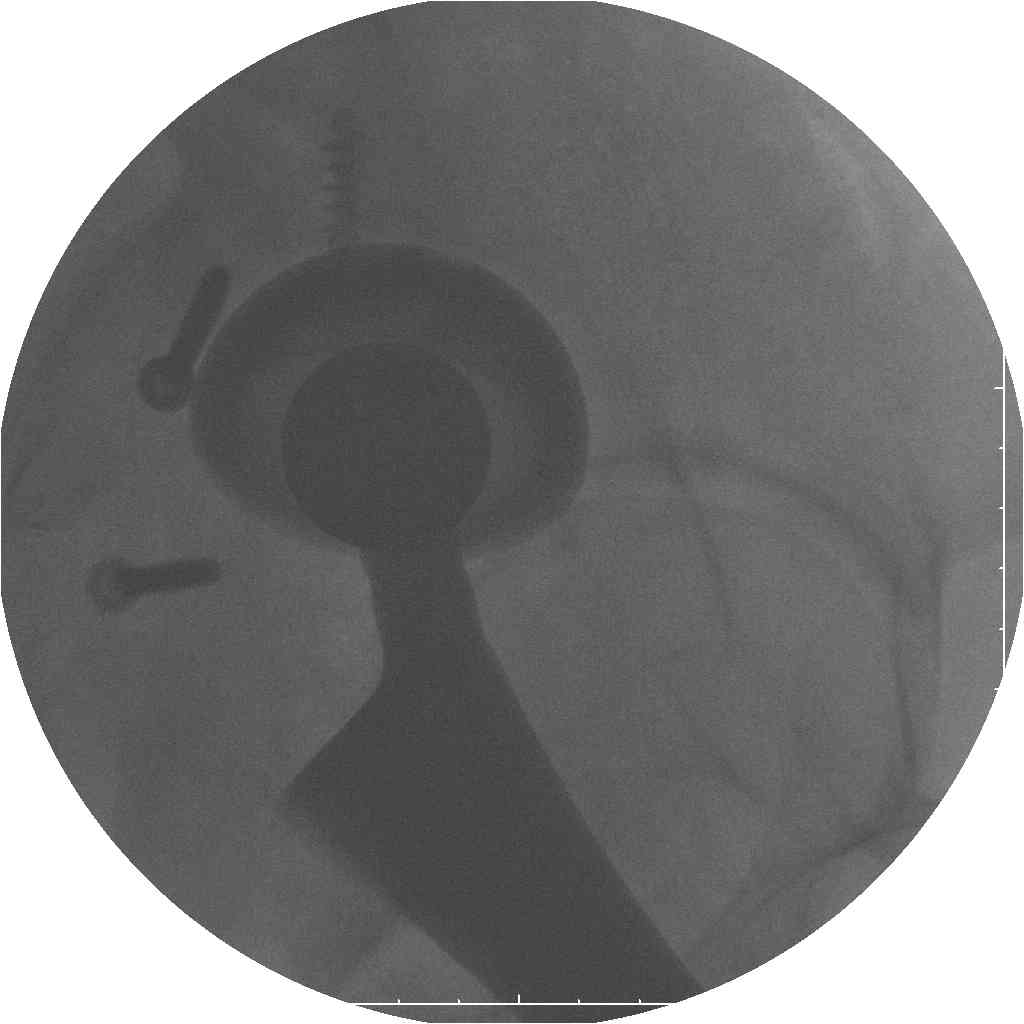

Уважаемые коллеги.В 3 Центральный Военный Клинический Госпиталь имени А. А. Вишневского, что в Красногорске, Московской области, в отделение эндопротезирования крупных суставов поступил пациент 1960 года рождения Жалобы при поступлении: на боли в области левого тазобедренного сустава (больной указывает на точку расположенная в середине условной линии между седалищным бугром и большим вертелом), усиливающиеся в начале ходьбы, при опоре на левую ногу с иррадиацией болей по наружной и наружно-задней поверхности левого бедра, левый коленный сустав; снижение объема движения в левом тазобедренном суставе, снижение опорной способности левой нижней конечности, хромоту на левую ногу, необходимость использования дополнительной опоры (костыли) при ходьбе, снижение объема двигательной активности из за болей в суставе.В анамнезе: Со слов больного, согласно медицинских документов, в 1989 году получил травму левой нижней конечности: закрытый перелом левой вертлужной впадины с центральным вывихом головки левой бедренной кости. Лечился консервативное. В процессе лечения сформировался посттравматический артроз, укорочение левой нижней конечности до 5 см. 25.04.2005 года в Подольском Окружном Госпитале Министерства Обороны выполнено: одномоменто, остеосинтез заднего края вертлужной впадины фрагментом резецированной головки бедренной кости и тотальное эндопротезирование левого тазобедренного сустава бесцементным эндопротезом "VERSIS ET" с бесцементной чашкой TRILOGY. Послеоперационный период осложнился ранним нагноением области эндопротеза, в результате санаций очага инфекции и антибиотикотерапии, активного промывного дренирования антисептиками, послеоперационная рана зажила. После операции, со слов больного, через два месяца в полном объеме стал нагружать левую нижнюю конечность. В течение полгода, после операции чувствовал себя вполне удовлетворительно. С марта 2006года стал отмечать появление болей в области тазобедренного сустава, то в области паха, то в области левой ягодицы. С августа месяца отмечает те жалобы, с которыми он сейчас к нам обратился. Температура тела, после заживления раны, нормальная. В анализах крови, лейкоциты около 7 тыс, формула нормальная, СОЭ 12 мм ч. Локально: при осмотре обеих нижних конечностей, анатомическая ось конечности не нарушена; отмечено относительное укорочение левой н\конечности на 1.5 см., гипотрофия мышц левого бедра 3 см, голени 2 см, симптом. Объем движений в тазобедренных суставах: правый~ сгибание- 60 гр, разгибание-180 гр ,отведение- 35 гр, левый~ сгибание- 110 гр , разгибание-170 гр , отведение-15 гр. Контуры других суставов н/конечностей обычные, объем движений в них не страдает. Пульсация на артериях конечностей удовлетворительная. Неврологические нарушения конечностей отсутствуют, рефлексы на обеих н/конечностях одинаковые, чувствительных нарушений нет. Осевая нагрузка на левую нижнюю конечность вызывает боль в точке расположенная в середине условной линии между седалищным бугром и большим вертелом. Отмечается пигментация и пастозность нижней трети обеих голеней и стоп, характерная для посттромботической болезни. На Цветном дуплексном сканировании сосудов нижних конечностей: Нестенозирующий атеросклероз обеих бедренных и подколенных артерий . Гемодинамически значимых препятствий кровотоку в магистральных артериях ног не выявлено. Глубокие и поверхностные вены нижних конечностей проходимы. Умеренная недостаточность клапанов подколенных вен. Данных за тромбоз глубоких вен на момент осмотра не получено.А вот что пишет наш рентгенолог: На серии рентгенограмм области левого тазобедренного сустава определяется тотальный бесцементный эндопротез. Вокруг тени чашки эндопротеза определяется ободок остеорезорбции. Кроме того, визуализируется деформированный костный винт фиксирующий консолидированный отломок вертлужной впадины, вплотную прилегающий к тени чашки эндопротеза. Заключение: Рентгеновские признаки нестабильности чашки тотального эндопротеза. Лучевая нагрузка: 6 мЗв. У нас в отделении разошлись мнения: начальник мой утверждает, после сравнения снимков, принесенных больным от августа и октября 2006года и наших рентгенснимков, что у больного нет нестабильности вертлужного компонента, и что надо назначит курс консервативной терапии: препараты кальция, миакальцик, увеличить осевую нагрузку на левую нижнюю конечность, ЛФК направления на укрепление мышц бедра, ягодиц, физиолечение. А я утверждаю, что у больного клиника нестабильности вертлужного компонента, и необходима ревизия вертлужного компонента, не исключено даже наличие инфекции под чашкой эндопротеза (не смотря на отсутствие клинических признаков инфекции). В результате проводимой консервативной терапии, боли у больного усилились. Помогите рассудить нас, мы готовы выслушать ваши мнения по этому поводу. С уважением Батал Шушания.3 ЦВКГ имени А. А. Вишневского